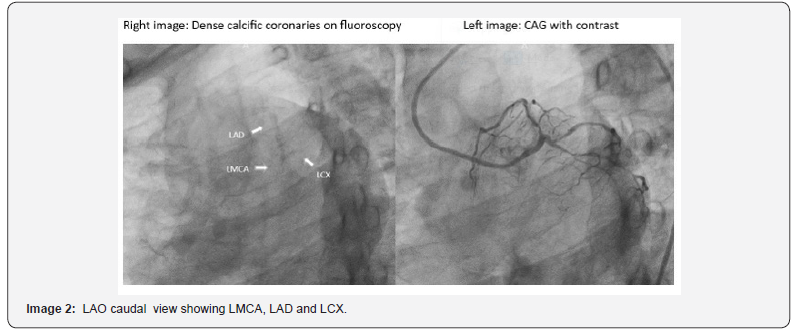

Coronary Angiogram: Suggestive of LMCA + Triple vessel disease (Images 1,2,3)

LMCA - Thick calcific vessel with 50% stenosis

LAD – (Type 3) Thick calcific vessel, ostio-proximal 90% stenosis, proximal to mid long segment 70-80% stenosis. Diagonal-1 large vessel, ostial disease, proximal 50% stenosis, distal 80-90% stenosis

LCX – (Non-Dominant) calcific vessel, proximal to mid two discrete lesions 80-90% stenosis. OM-1 large vessel, ostio-proximal 80-90% stenosis, mid 50% stenosis; OM-3 moderate size, proximal to mid two lesions 70-80% stenosis.